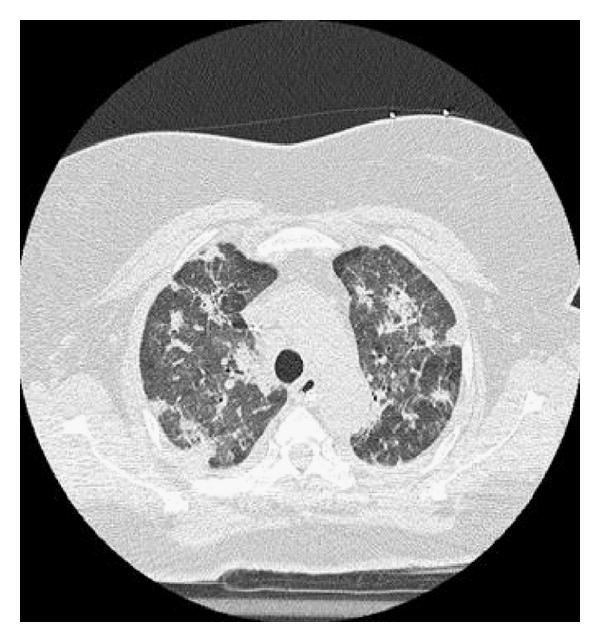

AIP was firstly described by Hamman and Rich in 1935 [22]. For many decades the patients in this first paper were assumed to have been suffering from UIP/IPF, in fact, it was 1990 when these patients were shown to truly suffer from AIP [23]. Clinically AIP presents as a rapid development of respiratory failure in a previously healthy person [24, 25]. Both clinically and radiologically, it usually displays the features of ARDS, but in contrast to ARDS, no specific cause as an aetiology can be found, therefore it could be considered as “idiopathic ARDS” [26, 27] (Figure 1(a)–1(d)). The histological pattern of AIP is typically DAD with hyaline membranes, edema, and interstitial acute inflammation [28]. In the organizing phase of DAD (approximately 5–10 days after injury), alveolar septal thickening with loose organizing fibrosis, type II pneumocyte hyperplasia, and patchy or diffuse airspace organization can be found (Figure 1(c)). The prognosis of AIP is dismal and the mortality high. It has been suggested that by adopting an aggressive diagnostic approach, that is, mechanical ventilation with a lung-protective strategy, and the early institution of immunosuppressive therapy it may be possible to improve the clinical outcome of AIP [29–31]. Controlled prospective studies on the treatment of AIP are not available, not surprising since AIP is so uncommon and it is generally a very acute lung manifestation displaying some overlapping features with ARDS.

(a)

(b)

(c)

(d)